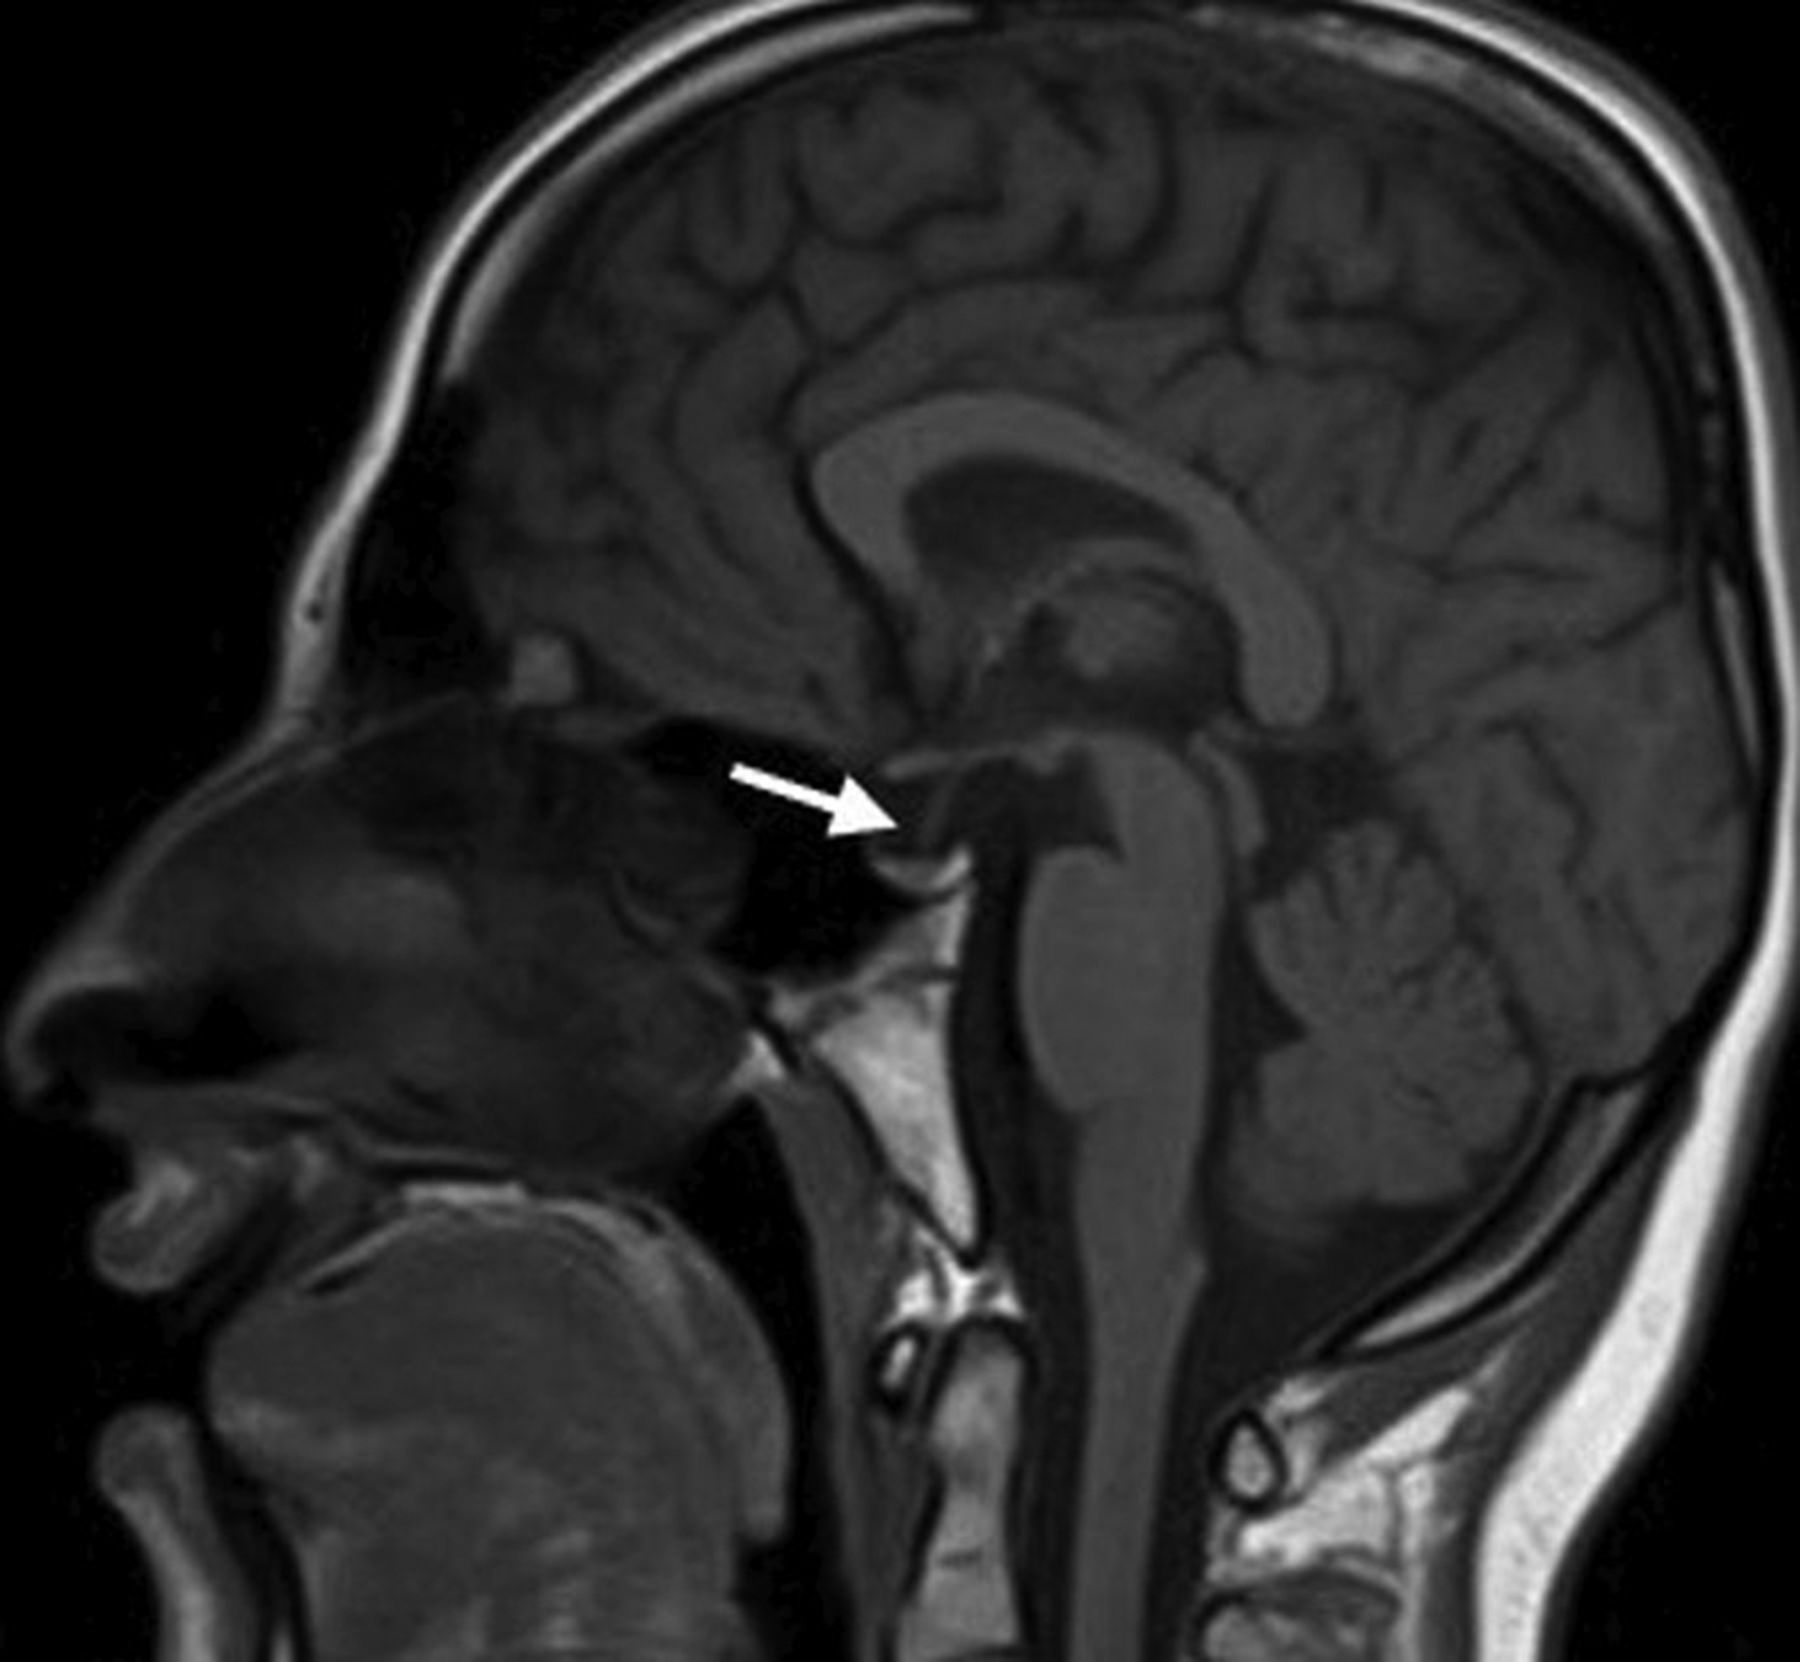

A partially empty sella and a small pituitary gland were seen in 20 patients (76.9%); they were the most common MR imaging abnormalities in our cohort (Fig 1). Patients with WSS had a significantly smaller mean pituitary gland volume of 173 ± 91 mm3 compared with healthy control subjects with a mean of 480 ± 85 mm3 (P < .005). Six patients (23%) had normal pituitary gland volume. The pituitary stalk varied in size, but most of the affected individuals had a relatively small stalk. No abnormal suprasellar and parasellar structures were noted.

Sagittal T1-weighted MR imaging for patient 22 shows a partially empty sella and a small pituitary gland (arrow).